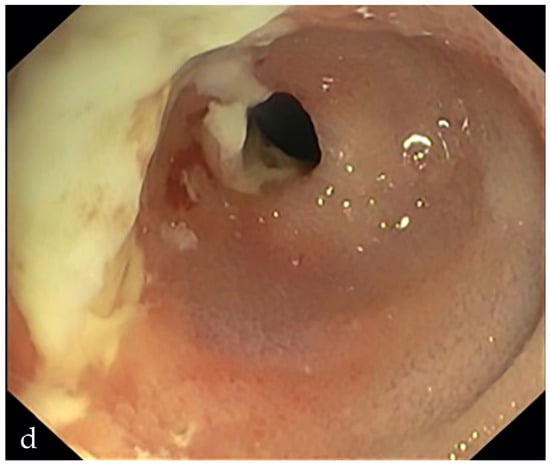

6. Is the Stricture Fibrotic or Inflammatory?